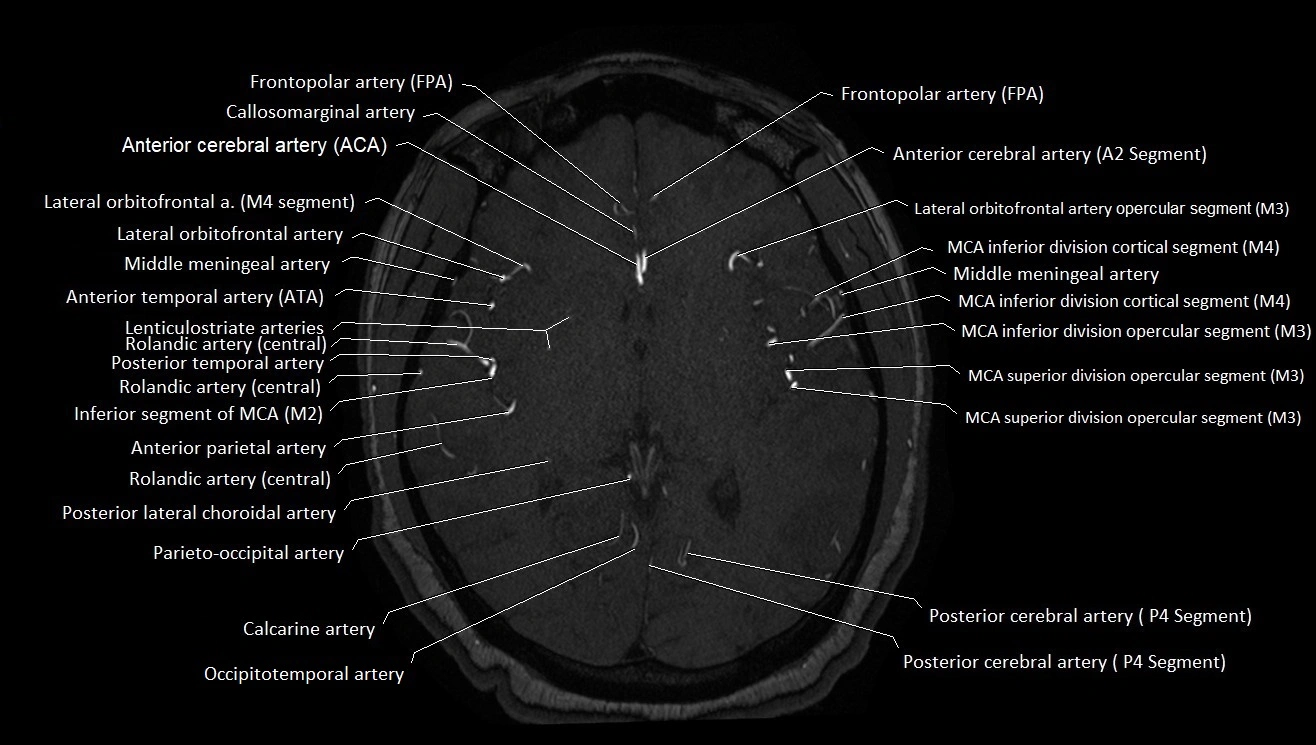

MRA (Magnetic Resonance Angiography):

• Flow-related enhancement makes the AChA appear as a bright, linear vascular signal against suppressed background

• High sensitivity for origin and proximal course; distal branches may be too small to resolve

• Detects stenosis, occlusion, aneurysm, AVM feeders

MRI images

image